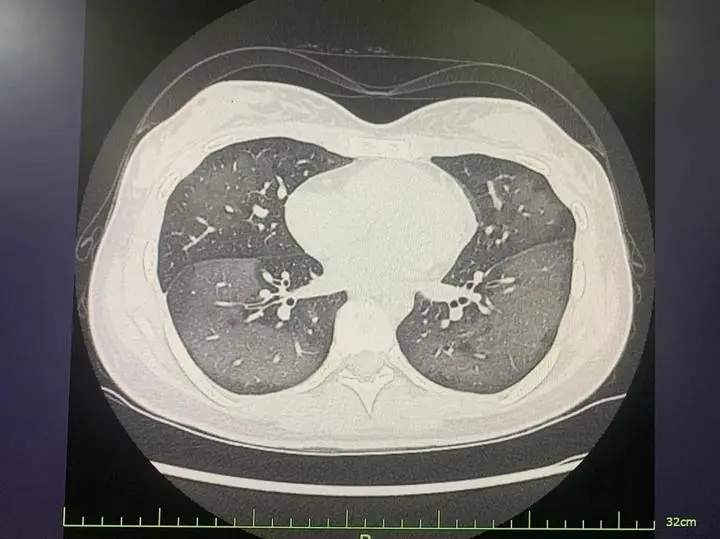

该院急诊科的主治医师童娅玲接诊了丽丽,经CT检查发现,丽丽的双肺呈现大范围白色样病变,报告提示“白肺”。

患者肺部CT

丽丽被诊断为“急性过敏性肺炎”,急诊专家对丽丽给予吸氧、激素抗炎抗过敏等对症支持处理后,急性症状得到缓解,她被收入呼吸内科病房进一步住院治疗。

急诊科主任陆远强主任医师解释,此类“白肺”与使用防晒喷雾时吸入的有害物质有关,喷雾中的某些化学成分会刺激诱发一系列过敏反应,从而导致广泛的气管、支气管乃至肺水肿,让肺部无法正常工作。

“白肺”一般是指重症肺炎在X线或CT检查下的表现,患者肺部呈现一大片的白色状态。“白肺”患者往往会出现呼吸困难、呼吸衰竭,严重者还会出现其它脏器功能障碍。